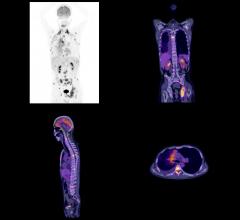

October 4, 2017 — Blue Earth Diagnostics recently announced the results of a pre-planned interim analysis from an ...